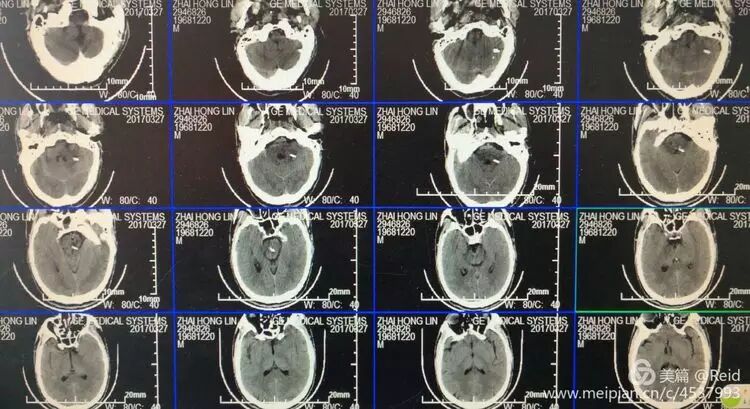

保守治疗72小时后,病情无明显改善,家属决定尝试外科手术干预,谨慎沟通后,以移动呼吸机辅助下,经CT引导精确定位置管手术。

术中将外径3.0mm的细引流管经乙状窦后小脑中脚(脑桥臂)植入桥脑血肿内,术中抽出1-2ml陈旧血肿。术后尿激酶注入融化固体血肿。

术后第5天复查头CT显示桥脑血肿清除满意。